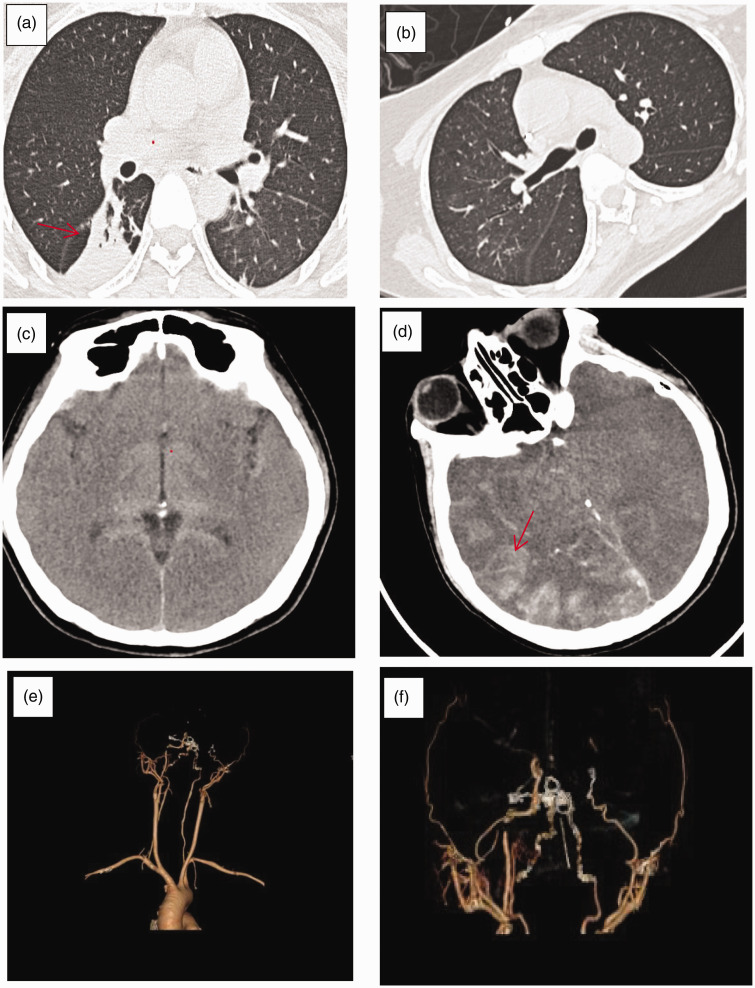

伊维菌素是一种经典的抗寄生虫药物,在世界各地广泛使用。2019冠状病毒病爆发后,许多研究报道了伊维菌素对2019冠状病毒病的潜在有效性;然而,由于证据不足和严重的副作用,世界卫生组织不建议使用这种方法。由于上述发现,近年来因滥用伊维菌素引起的中毒和其他严重反应的报告数量有所增加。值得注意的是,迄今为止尚未报告有血药浓度记录的经皮伊维菌素中毒病例。我们报告了一个罕见的伊维菌素误用致死病例,并回顾了最近的文献。患者因经皮过量服用伊维菌素而中毒。患者血药浓度为27 ng/mL。临床表现以早期胃肠道症状为主,晚期以弥漫性脑水肿和颅内高压为主。尽管进行了积极的治疗,包括血液灌流和心肺支持,患者还是死亡了。最近的许多体外研究表明,伊维菌素有可能成为一种新的抗癌药物。如果临床研究证明其抗癌效果,也可能导致伊维菌素的过度使用。本研究旨在提高临床医生和公众对伊维菌素中毒的认识,从而防止药物滥用。

Ivermectin is a classic antiparasitic drug that is widely used around the world. After the outbreak of coronavirus disease 2019, many studies have reported the potential effectiveness of ivermectin against coronavirus disease 2019; however, it is not recommended by the World Health Organization because of insufficient evidence and significant adverse effects. Owing to the abovementioned findings, the number of reports of poisoning and other serious reactions caused by ivermectin abuse have increased in recent years. Notably, no previous cases of transdermal ivermectin poisoning with documented blood concentrations has been reported to date. We report a rare fatal case of ivermectin misuse with a review of recent literature. The patient suffered from ivermectin poisoning due to transdermal overdose. The patient's plasma concentration was 27 ng/mL. The main clinical manifestations were gastrointestinal symptoms in the early stage and diffuse cerebral edema and intracranial hypertension in the later stage. Despite active treatment, including hemoperfusion and cardiorespiratory support, the patient died. Many recent in vitro studies have shown that ivermectin has the potential to become a new anticancer drug. If clinical research proves its effectiveness against cancer, it may also lead to ivermectin overuse. This study aimed to raise awareness regarding ivermectin poisoning among clinicians and the public, thereby preventing drug abuse.